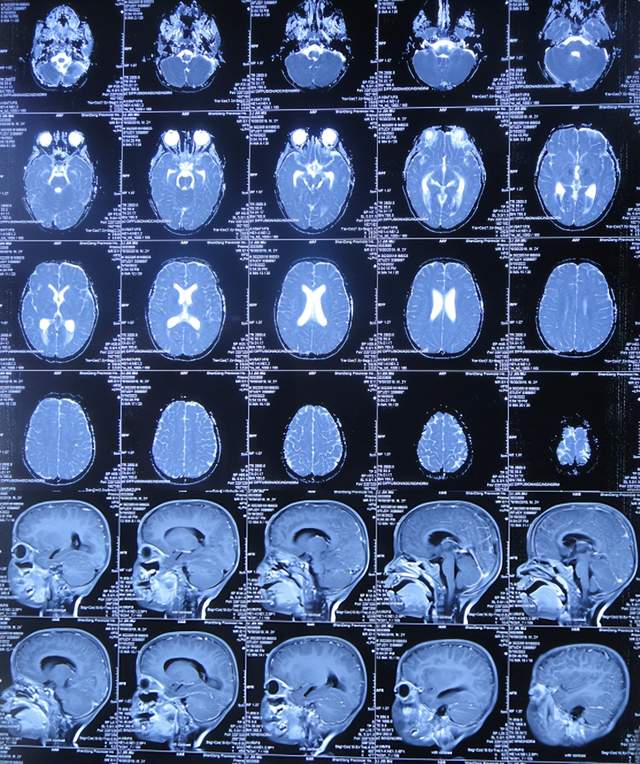

住院治疗7天即2022年5月18日,出现头痛,呕吐,体温再次升高为39.6度,心电图示室性心动过速,室早,考虑“心肌炎”,查头颅核磁(图-1)后并行腰穿见脑脊液呈金黄色,留取脑脊液送常规化验提示诊断为颅内感染,给予抗感染治疗。

图-1:2022年5月18日头颅核磁